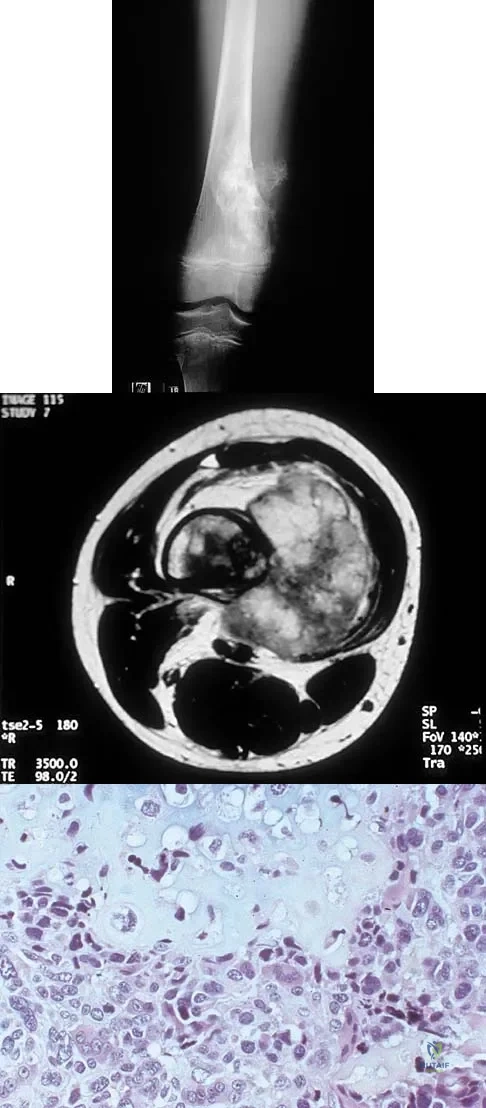

A 16-year-old girl has had pain in the left groin for the past 4 months. She notes that the pain is worse at night; however, she denies any history of trauma and has no constitutional symptoms. There is no history of steroid or alcohol use. Examination reveals pain in the left groin with rotation of the hip. There is no associated soft-tissue mass. A radiograph and MRI scan are shown in Figures 32a and 32b, and biopsy specimens are shown in Figures 32c and 32d. What is the most likely diagnosis?

Explanation